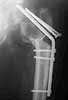

Now he re-admitted with the images 3,4.

What would you do in the situation?